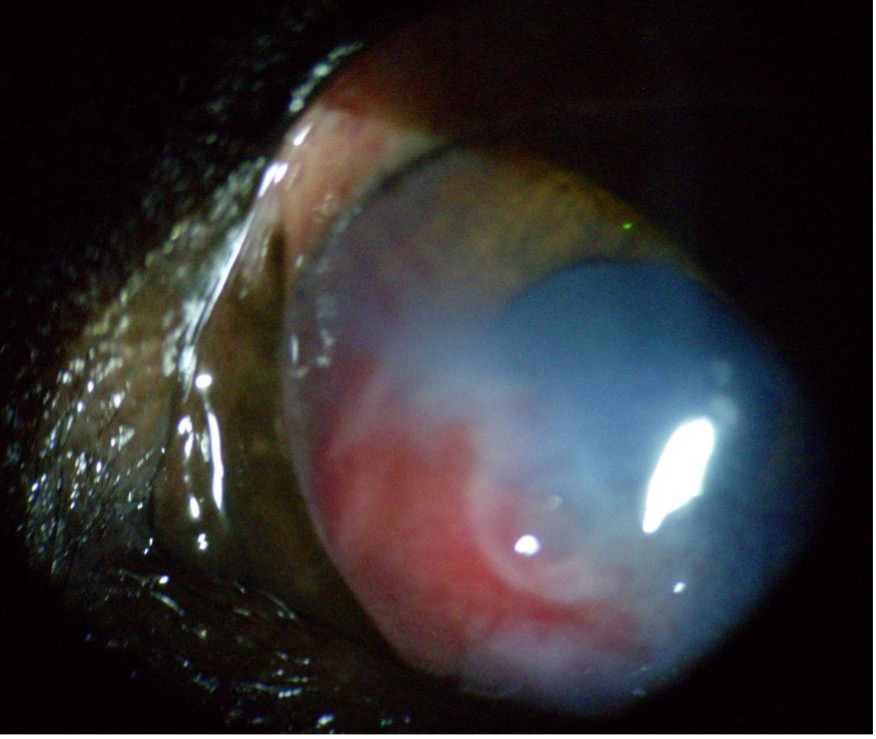

- Ectopiás cilia – Ez egy súlyosabb forma, amikor egy vagy több szempilla a szemhéj belső oldalán, a kötőhártya felől nő, közvetlenül a szaruhártyához érve. Ezek a szőrszálak állandó irritációt okoznak, és gyakran fekély kialakulásához vezetnek.

- Kötőhártya-gyulladás, szemvörösség

- Fekély a szaruhártyán (ami már fájdalmas és sürgősségi ellátást igényelhet)

A distichiasis és az ectopiás cilia szemészeti vizsgálattal ismerhető fel. Ehhez gyakran réslámpát vagy nagyítót, valamint fluoreszcein-es festést alkalmaznak a szaruhártya elváltozásainak vizsgálatához.

- Sebészi kimetszés súlyosabb vagy ectopiás szempilla esetében